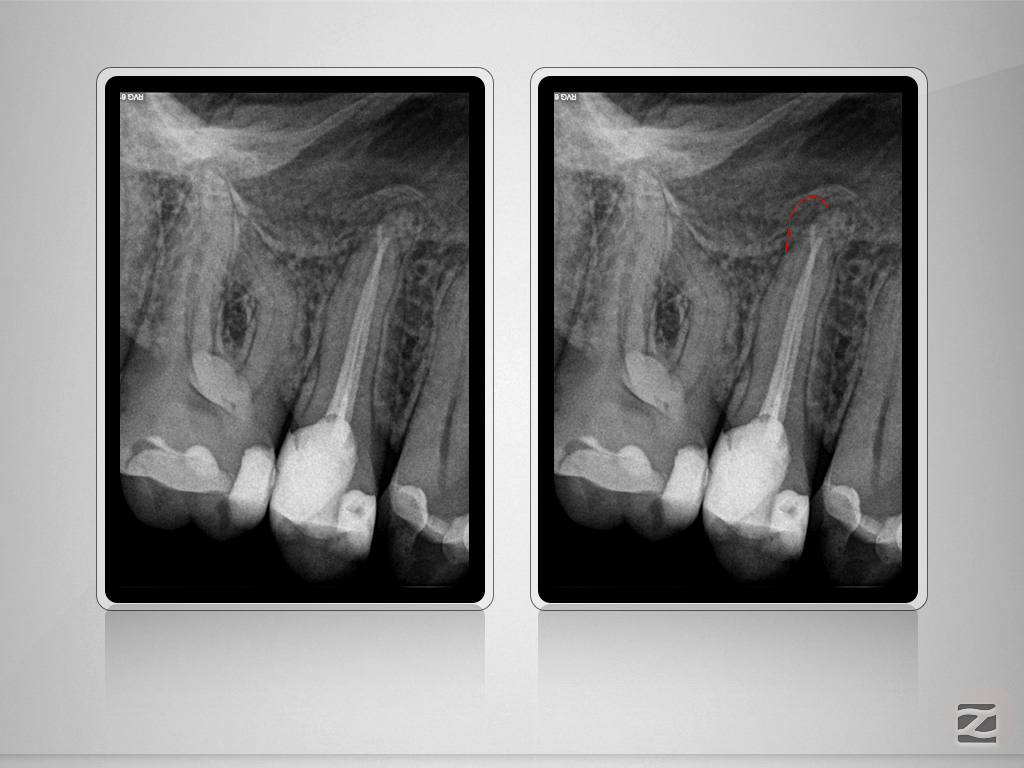

15D.012 Veröffentlicht 9. Januar 2018 am 1024 × 768 in Immer schön skeptisch bleiben. Das Recall. Überfüllt oder nicht?